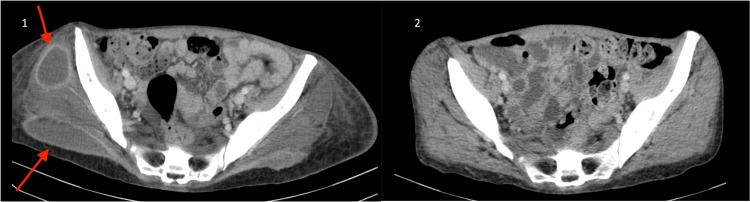

Pyomyositis is a bacterial infection deep within the muscles, often leading to multiple intramuscular abscesses. While historically linked with tropical regions, its incidence in temperate zones has been increasing, primarily due to factors such as immunosuppression. Typically, it manifests as a subacute infection, although when caused by Group C and resulting in toxic shock syndrome, it can lead to poorer outcomes. Here, we report a rare case of extensive multifocal bilateral pyomyositis in an immunocompetent young woman, preceded by toxic shock syndrome.

脓性肌炎是一种发生于肌肉深层的细菌感染,常导致多发性肌内脓肿。虽然过去认为其与热带地区有关,但在温带地区其发病率一直在上升,主要是由于免疫抑制等因素。通常,它表现为亚急性感染,不过当由C组细菌引起并导致中毒性休克综合征时,可能会导致更差的预后。在此,我们报告一例罕见的广泛多灶性双侧脓性肌炎病例,该病例发生在一名免疫功能正常的年轻女性身上,之前出现了中毒性休克综合征。